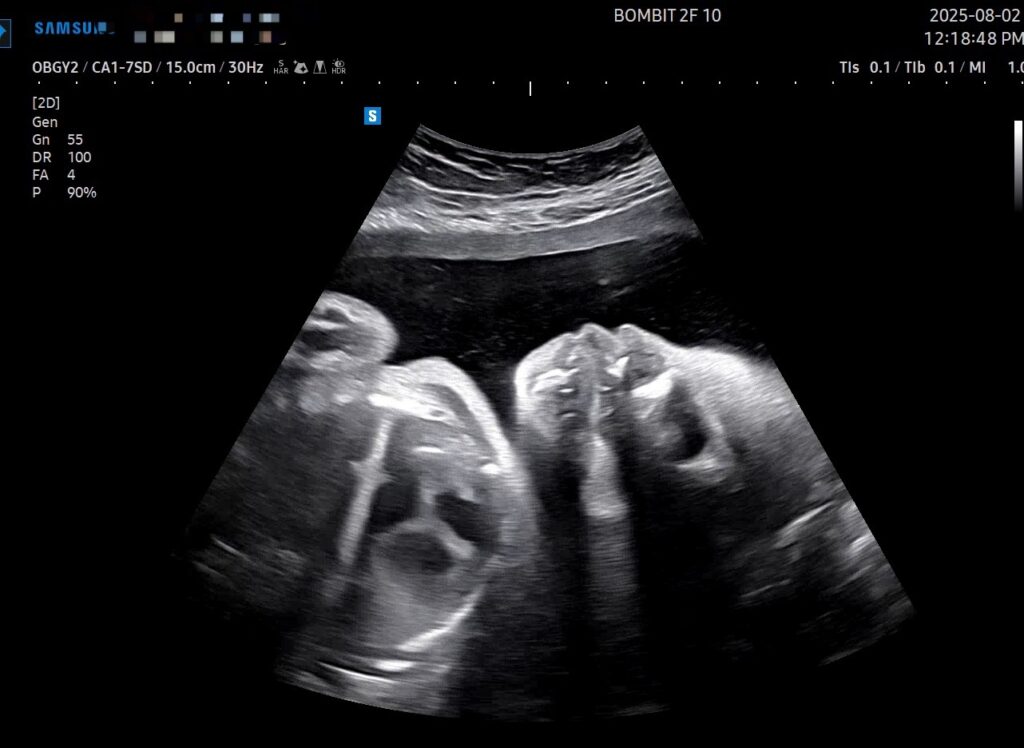

우선, 단비는 기특하게도 돌았다! 이제 더 이상 역아가 아니란다. 기특한 우리 단비!

그리고 크기는.. 초음파에서 확인했듯 더 더 우량해졌다 -_-;;

29주 6일차의 초음파인데, 몸무게, 배 둘레, 다리 길이 기준으로 주수는 약 32주로 나온다.

전반적으로 뼈대가 크면서 배도 나온(=살도 잘 붙은) 그런 아기인 듯.